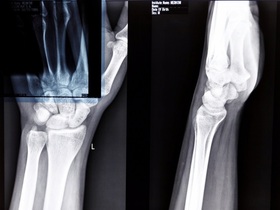

Инструментальная диагностика подагры:

- УЗИ суставов и почек;

- рентген "целевых" суставов;

- двойная энергетическая компьютерная томография суставов;

- МРТ.

Дифференциальная диагностика проводится с септическим, пирофосфатным, реактивным, псориатическим, ревматоидным, посттравматическим артритами, с периферической формой спондилоартрита, флегмоной, рожистым воспалением, остеоартрозом.